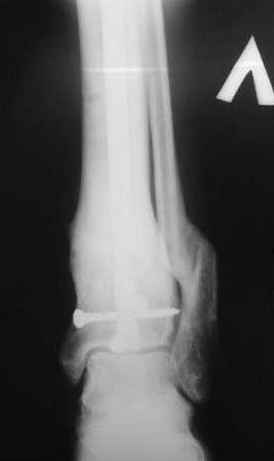

Произведено ПХО, acute shortening (5 см), фиксация стержневым аппаратом Hoffman.

3,4 - через 4 недели наложен спице-стержневой аппарат, произведена остеотомия большеберцовой кости в верхней трети, раны зажили, проводилась дистракция в аппарате.